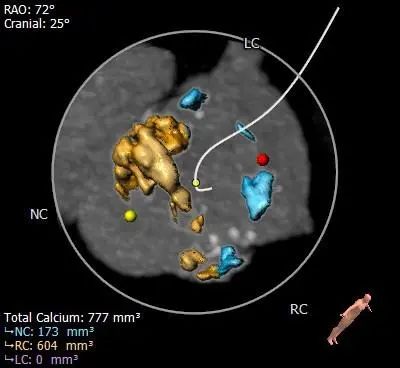

Type 0型二叶式主动脉瓣,重度钙化,无冠窦瓣叶边缘靠近左冠侧钙化较重呈团块状,钙化向对合边缘及流出道延伸,前窦钙化分布于窦内,瓣叶不规则增厚粘连。

HU850

HU1000